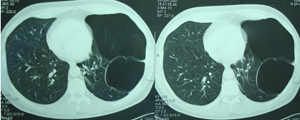

Εικόνα 1.

Οπισθιοπροσθία ακτινογραφία θώρακος. Διακρίνονται ευμεγέθεις

αερώδεις κύστες που καταλαμβάνουν, σχεδόν ολόκληρο το αριστερό

ημιθωράκιο. Ο ασθενής είχε αίσθημα δύσπνοιας μετά από προσπάθεια.